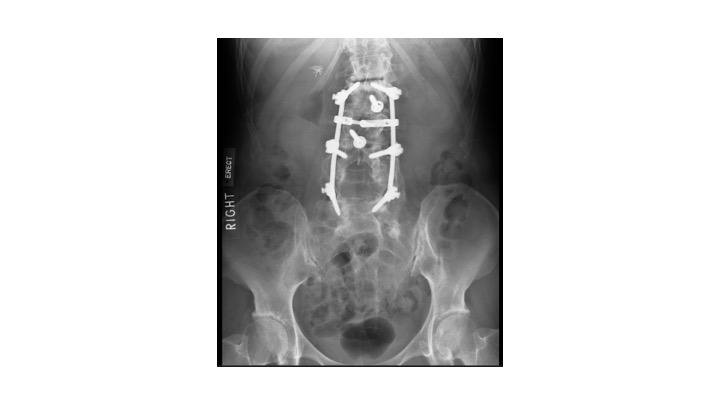

A 63-year-old female presented with recurrent THA instability - verbal consent was obtained for this report. She underwent L2-S1 posterior stabilization with L2-L3 anterior lumbar interbody fusion in May 2002 (Figure 1) and an uncomplicated right THA in April 2007. (Figures 2a-b) Five years following primary THA (July 2011), the patient sustained her first THA dislocation, which was treated with a closed reduction. Between 2011 and 2018, the patient had seven repeat episodes of hip instability – in 2012, one was complicated by a peri-prosthetic femur fracture requiring three revisions and reconstruction with a trochanteric claw plate. She was subsequently diagnosed with a prosthetic joint infection (PJI) which required an antibiotic spacer and subsequent re-implantation three months later. (Figures 3a-b) Following treatment of initial instability and femur fracture, the implants included a size 16 standard taper femoral stem and a 50-mm acetabular shell with 32-mm liner.

In addition to the multiple revision THAs, our patient was concomitantly being treated for continued sagittal plane imbalance and spinal stenosis. In August 2016, the patient underwent posterior instrumentation of the T9-L4 vertebrae as well as direct lateral interbody fusion of the T12-L2 disc spaces. In July 2018, the patient underwent cervical instrumentation of the C3-T1 vertebrae to treat myelopathy, which was extended to include C2-C3 anterior/posterior spinal fusion in September 2020 to address instability. Erect, lateral spine radiographs were recorded and demonstrate a pelvic incidence of 54ºwith a pre-operative lumbar lordosis of 33º (PI-LL mismatch of 21º indicating a severe sagittal spinal deformity) and a post-operative lordosis of 46.9º. (Figures 9a-b) While these radiographs represent a physiological alignment, the resulting stiffness could explain the recurrent THA instability.